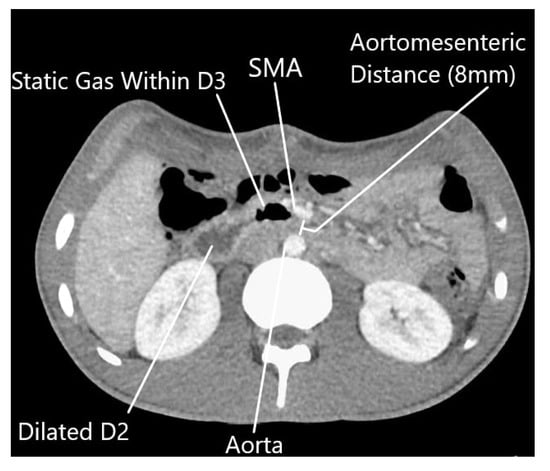

The patient underwent resection of the 11.1 kg, 70 cm mass without en bloc visceral resection; surgical margins were negative with no capsular disruption or intra-operative tumor spillage. It is worth noting that the duodenum was visualized crossing the midline, and the ascending, transverse, and descending colons were in their normal anatomic positions, excluding pre-existing malrotation. At the conclusion of the resection, he was noted to have near-complete absence of lipomatous tissue in his retroperitoneum. Post-operatively, he was persistently intolerant of diet advancement; despite apparently successful attempts at nasogastric decompression with evidence of bowel function, he demonstrated persistent bilious emesis with a benign abdominal exam. An upper gastrointestinal series revealed abrupt cutoff of contrast in the mid-duodenum, with significantly delayed transit of contrast distally (Figure 2). Abdominal CT demonstrated duodenal compression by the SMA with a reduced aortomesenteric distance of 8 mm, diagnostic of SMA syndrome (Figure 3). A nasojejunal feeding tube was placed fluoroscopically; the patient quickly tolerated goal tube feeds and began gaining weight. He remained nil per os for 4 weeks after discharge with continued weight gain, before slowly resuming oral intake. The patient’s intolerance to oral intake has resolved; he is now independent of tube feedings and has returned to near the 50th weight percentile for his age and height.

Figure 3. Abdominal computed tomography scan showing post-operative return of superior mesenteric artery to normal anatomic position, with reduced aortomesenteric distance (8 mm). (SMA—superior mesenteric artery, D2—second portion of the duodenum, D3—third portion of the duodenum).